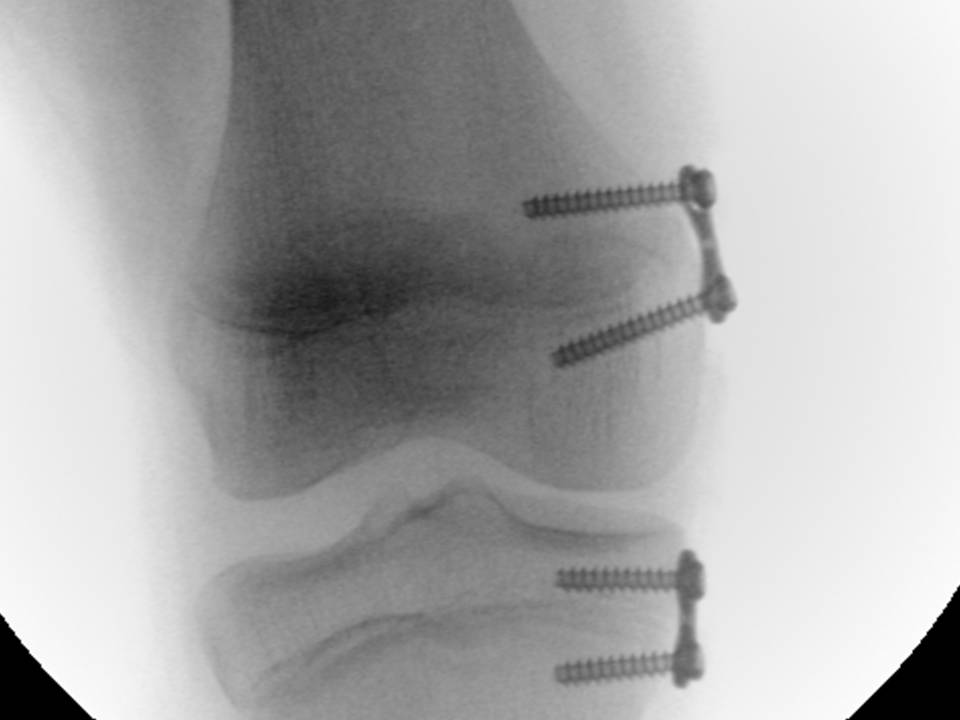

← Precedente Successivo → Fig. 12C: aspetto RX dopo impianto delle placche sul versante mediale della cartilagine coniugale del femore e della tibia. Mi piace Caricamento...